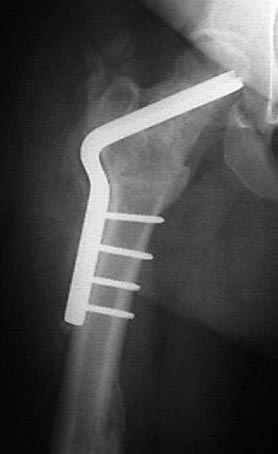

На рисунке N1 предоперационный план лечения ложного сустава шейки бедра- линия ложного сустава, угол и направление введения импланта, клиновидная остеотомия в градусах и миллиметрах, второй снимок после коррекции, расчет, на сколько удлиняется конечность и размеры импланта;

N3 рисунок окончательный снимок, после операции моя рентгенограмма должен выглядеть примерно как эта картина. На N4 снимке клин перед удалением; N5 послеоперации 3 нед.; N6 окончательная рентгенограмма.

варус при проксимальном отделе 95 градусной пластиной.